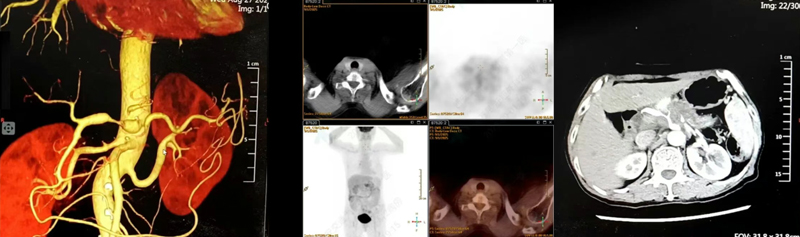

术后超声造影显示肿瘤部位呈无血供现象,周边血管结构保存完整,消融效果良好且安全。消融完成后,术者退出电极针,手术顺利结束,术后给予对症支持治疗,患者恢复良好。

术后即刻造影▲